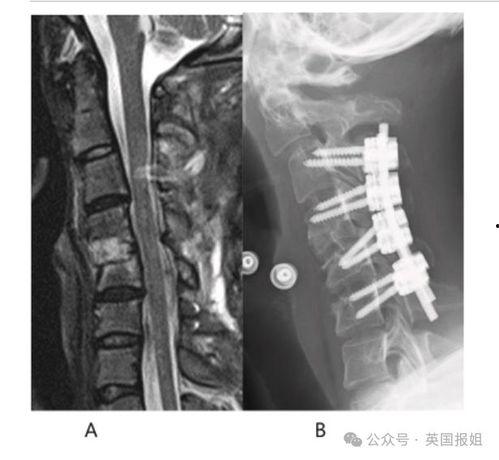

4. 手术:对于严重的颈椎病,日本人会选择手术来治疗。不过,手术风险较大,因此他们会慎重考虑。